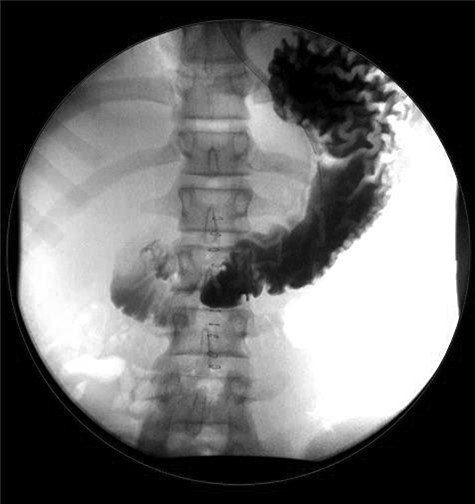

Case 1: A 14-year-old boy with a 2-day history of mild abdominal pain presented to the emergency department (ED) within 6 hours of sudden-onset severe abdominal pain, persistent, mostly in the periumbilical area. He denied nausea, vomiting, diarrhea, fever, melena and hematochezia. Past medical history only significant for ADHD on Adderall. On exam, he appeared in severe distress, with normal vital signs, diffuse abdominal rebound tenderness and rigidity. Laboratories revealed elevated white blood cell count (WBC) of 14.900/L and normal C-reactive protein. Abdominal ultrasound was unremarkable, but since the concern for acute abdomen, a computer tomography (CT) of the abdomen and pelvis was obtained, demonstrating a large pneumoperitoneum predominantly in the upper abdomen suggestive of perforated viscus (Fig. 1).

(a) CT abdomen and pelvis axial view. (b) CT abdomen and pelvis coronal view: there is a large pneumoperitoneum predominantly in the upper abdomen.